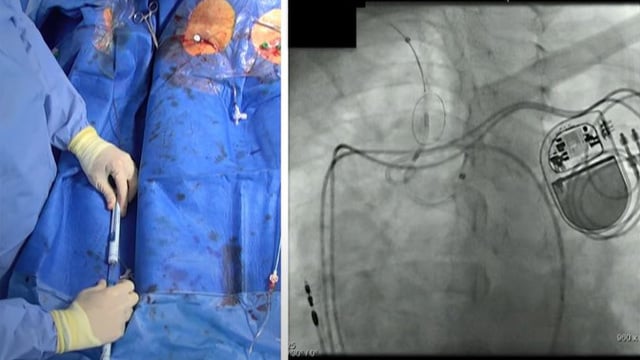

Stroke prevention - featured cases

Dive into this session featuring selected clinical cases from PCR London Valves 2024, focusing on the use of various stroke prevention strategies during structural heart interventions. Explore techniques such as snaring-assisted TAVR under cerebral embolic protection, single-side access for cerebral embolic protection devices, and the integration...

TAVI - stroke

Join this session for key perspectives on stroke management and prevention in TAVI: gain a comprehensive view of the long-term outcomes in transfemoral TAVI complicated by stroke, evaluate a novel cerebral embolic protection during TAVI through the PROTEMBO C-TRIAL, learn how TAVR debris captured by CEP...

Cerebral protection devices

Consult the slides on this page to analyze the use of a latest-generation cerebral protection device, observe a transcatheter mitral valve-in-valve performed with cerebral protection in a TAVR case, or appreciate the value of cerebral protection in an anomalous aortic arch.

Cerebral embolic protection during TAVI: evidence meets practice

Watch the replay of this webinar with D. Mylotte, C. Cook and R. Kharbanda to know more about the incidence and impact of TAVI associated stroke and much more!